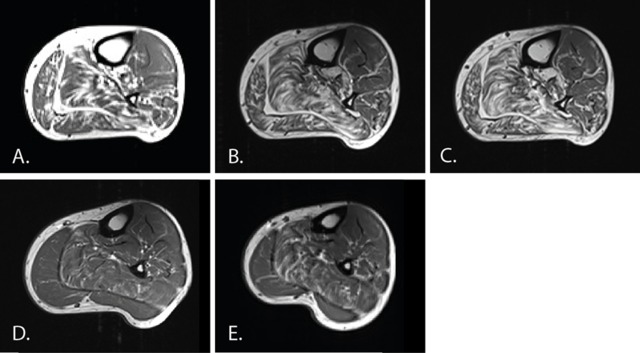

PURPOSE OF REVIEW: Charcot-Marie-Tooth disease (CMT) is one of the commonest inherited neuromuscular diseases with a population prevalence of 1 in 2500. This review will cover recent advances in the genetics and pathomechanisms of CMT and how these are leading to the development of rational therapies. RECENT FINDINGS: Pathomechanistic and therapeutic target advances in CMT include the identification of the ErbB receptor signalling pathway as a therapeutic target in CMT1A and pharmacological modification of the unfolded protein response in CMT1B. In CMT2D, due to mutations in glycyl-tRNA synthetase, vascular endothelial growth factor-mediated stimulation of the Nrp1 receptor has been identified as a therapeutic target. Preclinical advances have been accompanied by the publication of large natural history cohorts and the identification of a sensitive biomarker of disease (muscle MRI) that is able to detect disease progression in CMT1A over 1 year. SUMMARY: Advances in next-generation sequencing technology, cell biology and animal models of CMT are paving the way for rational treatments. The combination of robust natural history data and the identification of sensitive biomarkers mean that we are now entering an exciting therapeutic era in the field of the genetic neuropathies.